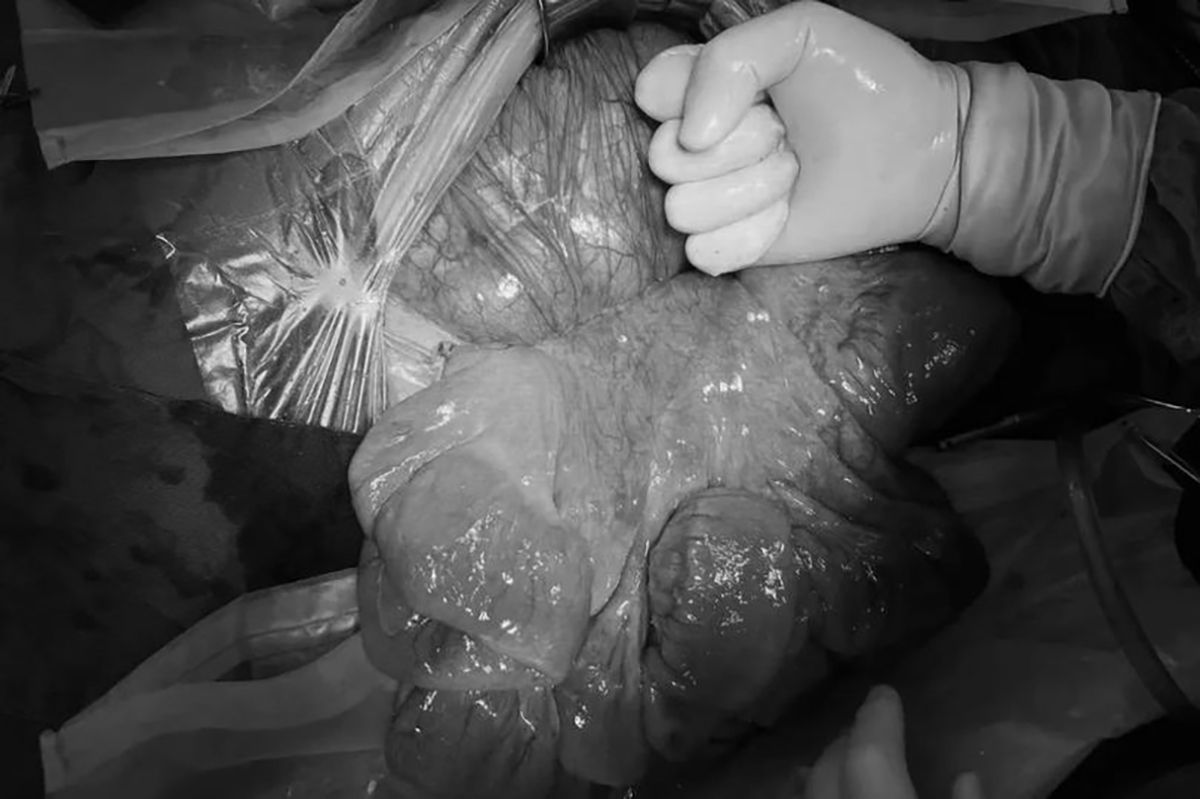

Medicii au îndepărtat fecale masive care cântăresc 20 kg, de la o femeie care suferea de constipație

Medicii care i-au efectuat operația au spus că au fost șocați după ce au examinat-o pe Hu, deoarece au descoperit că majoritatea organelor ei, inclusiv ficatul și stomacul, erau complet comprimate de intestinele umflate și umflate.

Potrivit medicilor, scaunul întărit al lui Hu cântărea 20 de kilograme și a fost comparat cu un piton lung de aproape un metru.